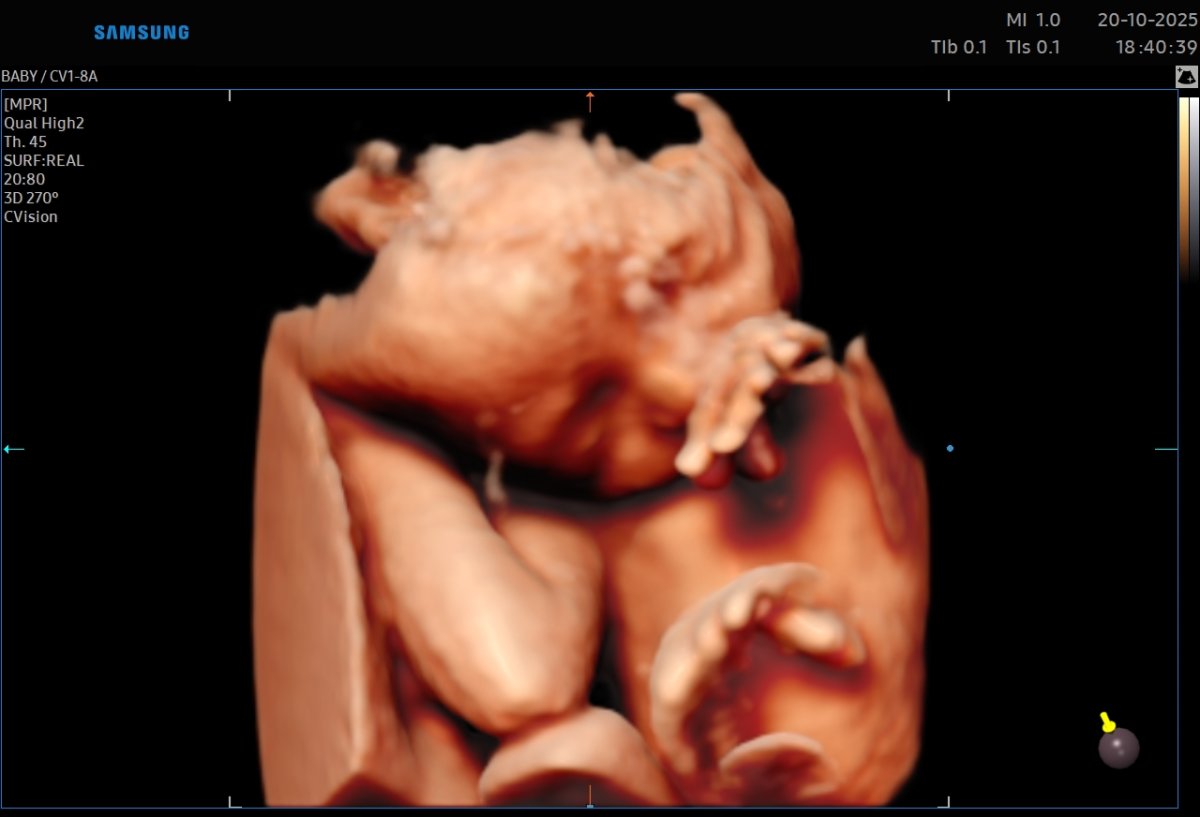

Gallerie de photos